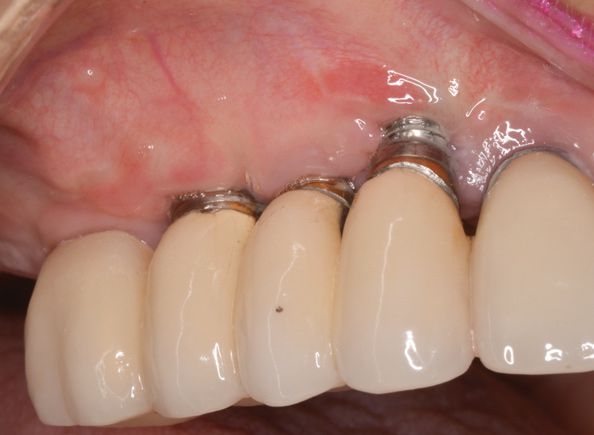

Периимплантит – одонтогенная инфекция, сопровождающаяся поражением мягких и костных тканей в области дентального имплантата и резорбцией кости. Клиника периимплантита характеризуется болью в области имплантата, гиперемией и отеком десны, образованием десневого кармана, кровотечением или гноетечением, подвижностью конструкции. Периимплантит диагностируется в ходе стоматологического осмотра с учетом жалоб, клинической и рентгенологической картины. Полноценное лечение периимплантита проводится поэтапно: 1 (консервативный) – удаление зубных отложений и устранение воспаления; 2 (хирургический) - очистка поверхности имплантата и костная пластика. В некоторых случаях показано удаление имплантата с последующей реимплантацией после необходимого лечения.

Мукозит, или периимплантное воспаление клинически проявляется набуханием и кровоточивостью десны, гиперплазией периимплантатной манжетки. Резорбции костной ткани при мукозите не происходит. В отличие от поверхностного воспаления, при периимплантите отмечается прогрессирующая убыль костной ткани. Больные жалуются на боль в области установленного имплантата, отек, гиперемию и кровоточивость периимплантатной десны; образование десневых карманов и свищей, из которых может выделяться гнойное содержимое.

При объективном обследовании пациентов с периимплантитом определяется гиперемия и отек мягких тканей. При зондировании десны отмечается кровоточивость; при пальпации периимплантатного кармана из него может выделяться гнойный экссудат. Имплантат подвижен; на соседних зубах и ортопедической конструкции выявляется скопление мягкого налета. Оценка состояния периимплантатной десны производится с помощью стоматоскопии.

Решающее значение в диагностике периимплантита и его степени принадлежит рентгенологическим исследованиям: прицельной дентальной рентгенографии, ортопантомографии и 3-мерной дентальной компьютерной томографии, с помощью которых выявляется резорбция костной ткани. Вспомогательную роль играют лабораторные исследования – микроскопическое, бактериологическое, морфологическое, ПЦР, биохимическое, рН-метрия ротовой жидкости.